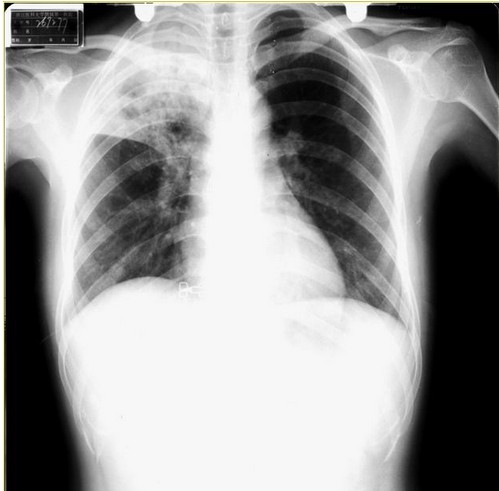

胸片

胸片经常用于检查胸廓(包括肋骨,胸椎,软组织等),胸腔,肺组织,纵隔,心脏等等的疾病。如肺炎,肿瘤,骨折,气胸,肺心病,心脏病。

胸片是临床应用最为广泛的检查之一。简便便宜。能筛查出很多疾病,比如肿瘤性疾病,很多老年人由于咳嗽,到医院照胸片检查,才发现有可疑肿瘤,便可进一步胸部CT检查以便进一步确定诊断。慢性阻塞性肺疾病病人突然出现胸痛,可能是气胸,此时体格检查一般可作出诊断,而快速胸片也可确定诊断。高血压性心脏病患者,胸片可见心脏增大。车祸病人,可能导致肋骨骨折,此时胸片可确定诊断,必要时还需要胸部CT进一步明确诊断。年轻人淋雨着凉后出现咳嗽、胸痛、咳痰等症状,怀疑肺炎,胸片可见大片高密度影,可确定为肺炎。长期慢性咳嗽的瘦弱女子,可能有肺结核,此时胸片也可提供证据,只要是肺尖有病灶。

胸片异常分类:1.太白(密度增高) 2.太黑(密度减低) 3.太大 4.位置异常

观片步骤:1.检查姓名和日期2.检查X光片透照条件 3.全面浏览胸片,罗列所有异常 5.仔细检查异常部位:胸壁、胸膜、肺内、纵隔内。

- 肺野:两侧肺野黑白程度应等同,识别水平裂及位置,走行于肺门与第6肋交腋前线水平。

- 肺门:左肺门高于右肺门2.5厘米,双侧肺门应向内凹陷,位于6~8肋间。

- 心脏:心脏最大横径应小于胸廓最大横径1/2。

- 纵隔:纵隔边缘除心膈角、肺尖、右肺门稍模糊外,其余应清晰可见。

- 膈肌:右侧膈顶高于左侧3厘米,膈顶应光滑。6.肋膈角应清楚锐利。

- 气管居中。

- 骨骼异常。

- 软组织有无增厚。

- 膈下区:胃泡,有无积气。